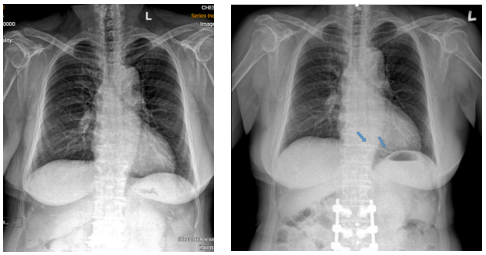

Hình 1: Hình X-quang ngực trước khi mổ cột sống (hình trái); Hình ảnh X-quang ngực thẳng thấy được dãy tăng sáng nằm ở vị trí tim phải (mũi tên) (hình phải).